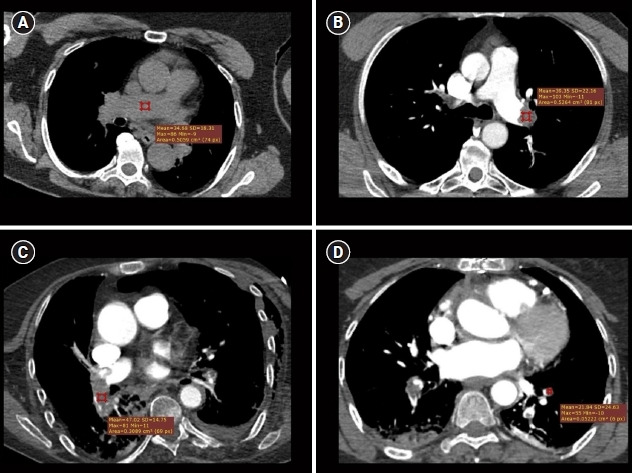

Objective: Pulmonary embolism (PE) is a vascular disease that is most frequently diagnosed using the radiological imaging technique computed tomography pulmonary angiography (CTPA). In this study, we aimed to demonstrate the diagnostic accuracy of the Hounsfield unit (HU) for PE based on the hypothesis that acute thrombosis causes an increase in HU value on CT.

Results: The study population (n=74) consisted of a study group (n=46) and a control group (n=28). The sensitivity and specificity of the HU value for predicting PE on thoracic CT were as follows: for the right main pulmonary artery, 61.5% and 96.4% at a value of 54.8 (area under the curve [AUC], 0.690); for the left main pulmonary artery, 65.0% and 96.4% at a value of 55.9 (AUC, 0.736); for the right interlobar artery, 44.4% and 96.4% at a value of 62.7 (AUC, 0.615); and for the left interlobar artery, 60.0% and 92.9% at a value of 56.7 (AUC, 0.736).

Conclusion: HU may exhibit high diagnostic specificity on CT for thrombi up to the interlobar level. An HU value exceeding 54.8 up to the interlobar level may raise suspicion of the presence of PE.